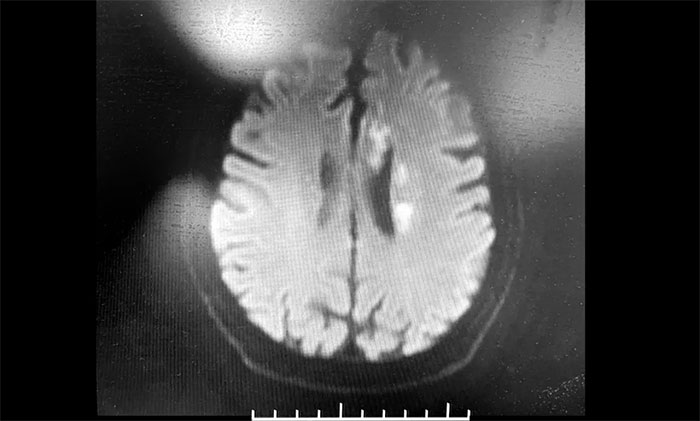

神經(jīng)內科3A病區(qū)周君主任詳細了解病史,查體,并為韓老伯完善相關的檢查。頭顱MRI示:腦干及雙側大腦半球多發(fā)陳舊梗死灶,左側胼胝體、半卵圓中心、側腦室旁及額葉多發(fā)梗死灶,偏亞急性期。腦動脈硬化,顱底動脈多發(fā)不同程度狹窄(左側頸內虹吸段為著)。

▲ 頭顱MRI示:左側多發(fā)梗死灶,左側頸內動脈狹窄

周君主任表示,從影像學上,患者左側腦室旁散在多個新鮮梗死灶,呈比較典型的“分水嶺樣梗塞”表現(xiàn)。分水嶺樣梗塞(Watershed infarction,WI),是指發(fā)生在腦部兩條主要動脈分布區(qū)的交界處的腦梗死,多發(fā)生于腦部較大動脈供血交界區(qū)。

韓老伯的新發(fā)病灶處在左側頸動脈供血支配范圍內,符合因左側頸內動脈狹窄而造成腦組織缺血表現(xiàn),需要針對這一引起腦梗的病因,及時采取干預治療措施。